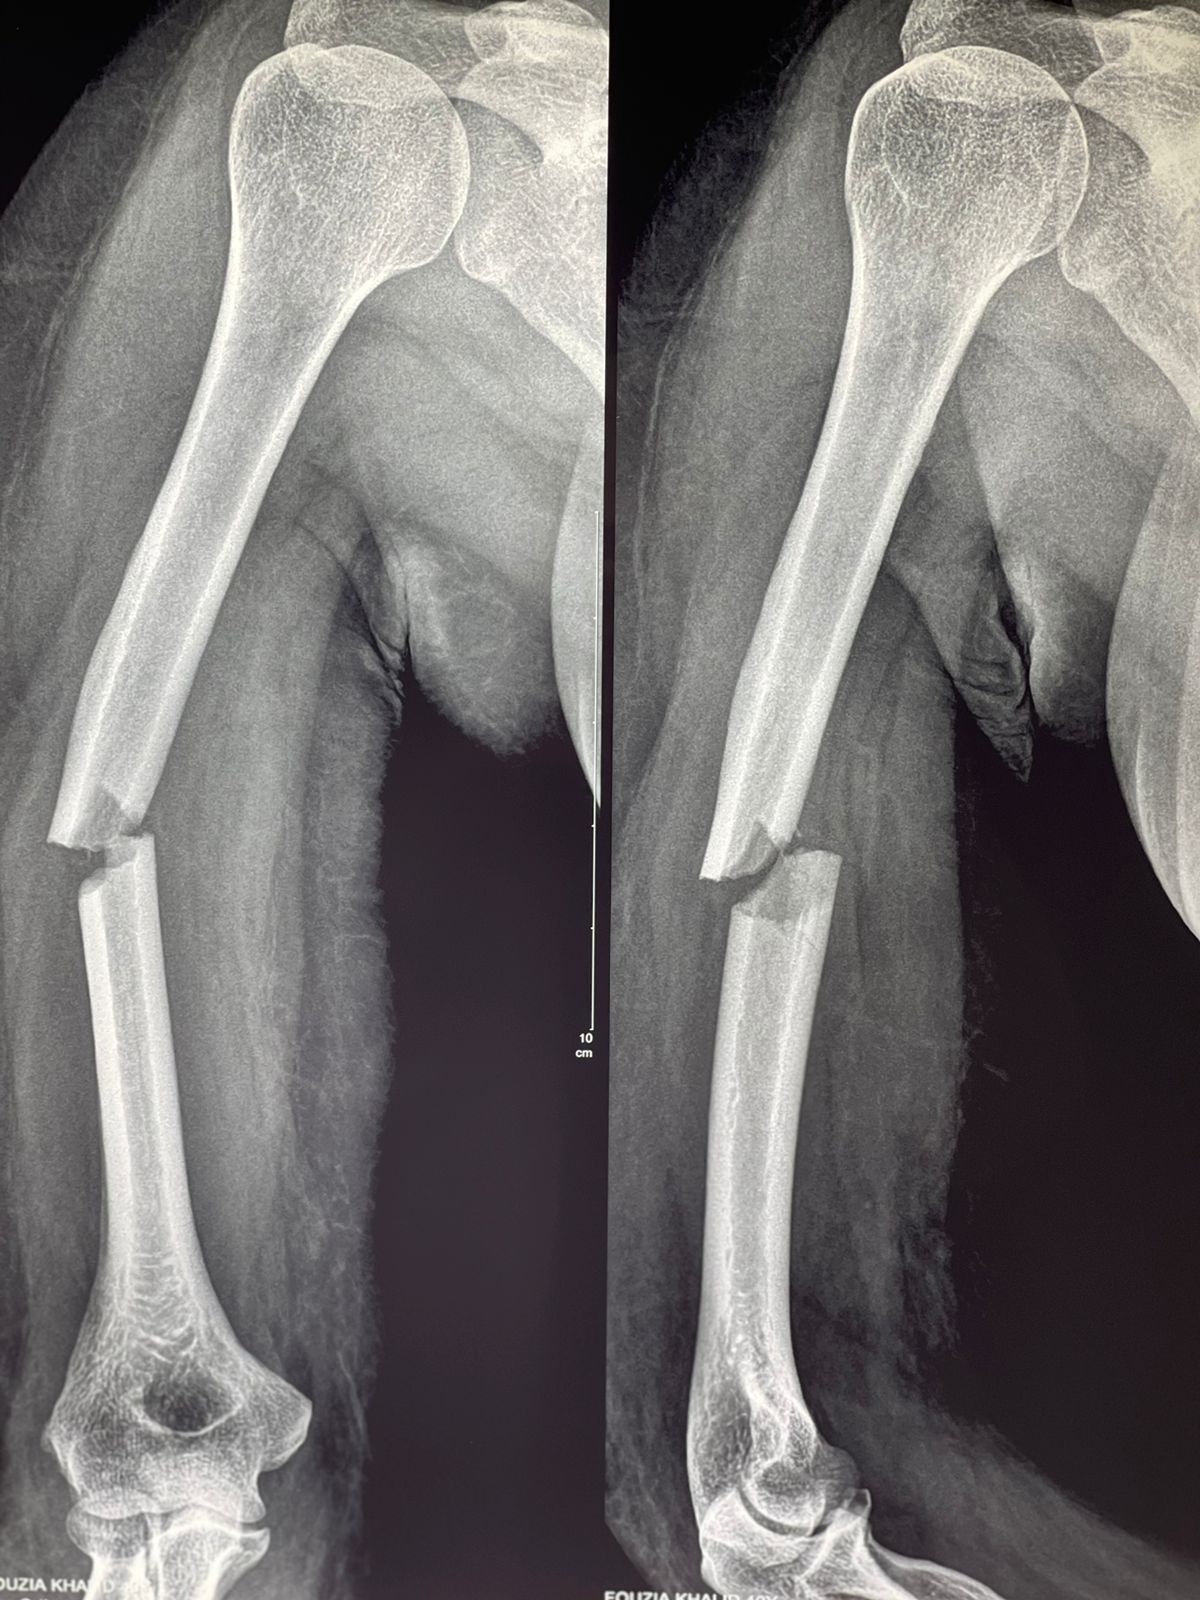

- Long bone fractures (arm, leg)

Fractures can occur due to accidents, sports injuries, falls, or overuse of certain joints and bones. They can also result from medical conditions like osteoporosis, which weakens bone density and makes them more prone to breaking.

A fracture usually causes sharp pain, swelling, bruising, and inability to move or bear weight on the affected area. A sprain, on the other hand, affects ligaments and may allow some movement.

Always seek a professional X-ray or medical evaluation for an accurate diagnosis.